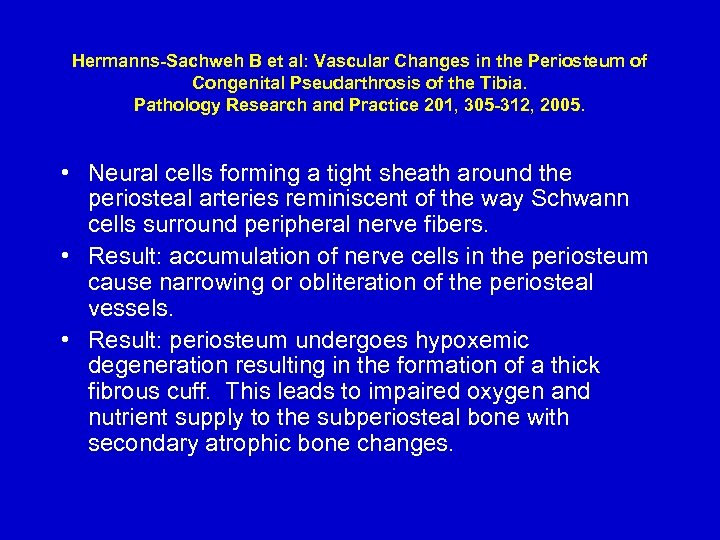

Hermanns-Sachweh B et al: Vascular Changes in the Periosteum of Congenital Pseudarthrosis of the Tibia. Pathology Research and Practice 201, 305 -312, 2005. • Neural cells forming a tight sheath around the periosteal arteries reminiscent of the way Schwann cells surround peripheral nerve fibers. • Result: accumulation of nerve cells in the periosteum cause narrowing or obliteration of the periosteal vessels. • Result: periosteum undergoes hypoxemic degeneration resulting in the formation of a thick fibrous cuff. This leads to impaired oxygen and nutrient supply to the subperiosteal bone with secondary atrophic bone changes.